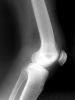

Egy tanulmány szerint a mérsékelt mértékű fogyás csökkenti a térd csont- és ízületi gyulladás (osteoarthritis) kialakulásának kockázatát.

Az Észak Karolinai Chapel Hill Orvosi Egyetem munkatársai felfedték, hogy a túlsúlyos emberek mintegy 5%-os súlyvesztése miatt csökken a kockázata térdízületi gyulladás kialakulásának. A térdízület gyakran betegszik meg középkorú és idős egyéneknél. Lauren Abbate és kutatócsoportja vizsgálatukat a Johnston Megyei Osteoarthritis Project adataira alapozták.

„Sokat hallottunk az elhízás szív- és érrendszeri betegségeket illetve cukorbetegséget okozó hatásáról, azonban az ízületi gyulladásban betöltött szerepét gyakran figyelmen kívül hagyják. Az osteoarthritis egy fájdalmas, legyengítő betegség. Csak korlátozott kezelési eljárások állnak rendelkezésünkre – igazából nem gyógyítható. Azonban, ha ezek az emberek lefogynak, csökkentik a kialakulás kockázatát, és mérsékelhetik a betegséghez kapcsolódó fájdalom mértékét” – nyilatkozta Lauren az Amerikai Reumatológiai Testület Philadelphiai tudományos ülésén.